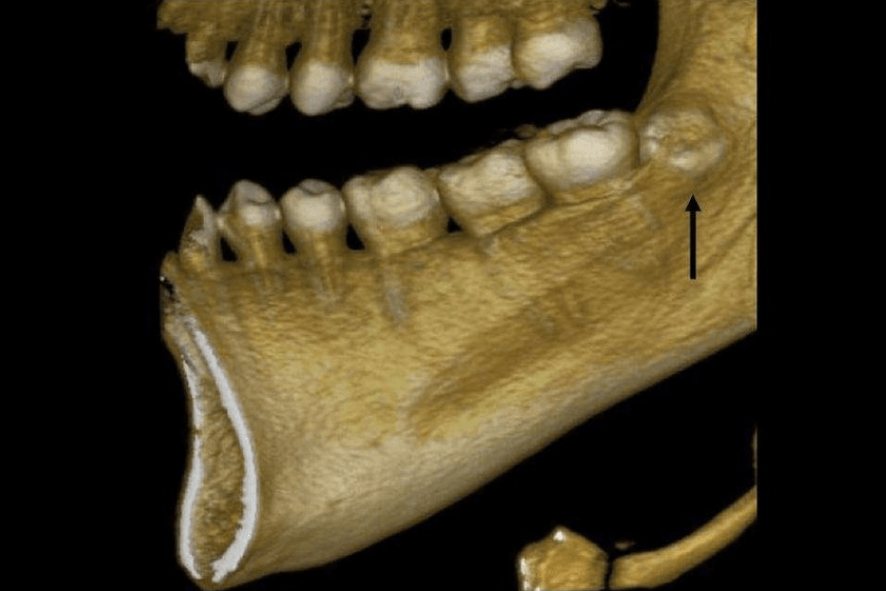

Um siso não é igual ao outro, eles têm dificuldades e riscos diferentes, por isso analisamos radiografias digitais, imagens de câmera intraoral e até tomografia computadorizada do dente siso.

Exames clínicos, radiografias, câmera intraoral e histórico de problemas de saúde. Em alguns casos, realizamos também tomografia do siso e solicitamos exames de sangue.

O valor da extração do siso em BH varia conforme a complexidade (nascido, semi-incluso, incluso), a necessidade de exames de tomografia e a necessidade de sedação. Na Santé, priorizamos que a cirurgia seja realizada por um cirurgião bucomaxilofacial, o que garante menos riscos, procedimentos mais rápidos e um pós-operatório mais tranquilo. O orçamento final é definido após avaliação clínica e radiográfica do siso (ou ciso).

Em média, cada siso leva 20 a 60 minutos para ser extraído, variando com a inclusão e anatomia. Cirurgias de siso/ciso incluso tendem a ser mais longas, mas o planejamento correto torna o procedimento previsível e seguro.

9) Quais os riscos e complicações mais comuns na extração do siso?

O cirurgião bucomaxilofacial é o profissional mais indicado para a extração de siso (ou ciso), especialmente em situações de dentes inclusos, mal posicionados ou próximos a nervos e estruturas delicadas. Graças à sua formação avançada em cirurgia, esse é o melhor dentista para tirar o siso, ele garante mais especialização técnica, agilidade no procedimento, menor risco de complicações e um pós-operatório mais rápido e confortável. Na Clínica Odontológica Santé, priorizamos que as cirurgias de siso sejam conduzidas por cirurgiões bucomaxilofaciais justamente para oferecer a máxima segurança, qualidade e tranquilidade em todas as etapas do tratamento.

O melhor profissional para realizar a extração do siso (ou ciso) é o cirurgião-dentista com título de especialização em cirurgia bucomaxilofacial. Esse cirurgião-dentista bucomaxilo tem formação avançada para lidar com casos complexos, como sisos inclusos ou próximos ao nervo, garantindo mais segurança, agilidade na cirurgia e menor risco de complicações.